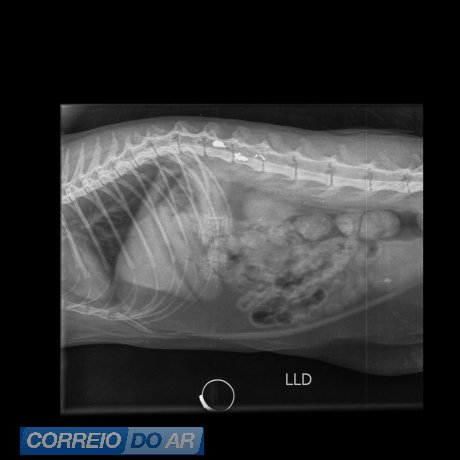

A gata foi socorrida e encaminhada para atendimento veterinário na clínica Vida Pets, onde recebeu os cuidados necessários. O animal passou por exames e procedimentos médicos após o disparo, enquanto os tutores prestaram depoimento às autoridades e acompanharam o andamento das investigações.